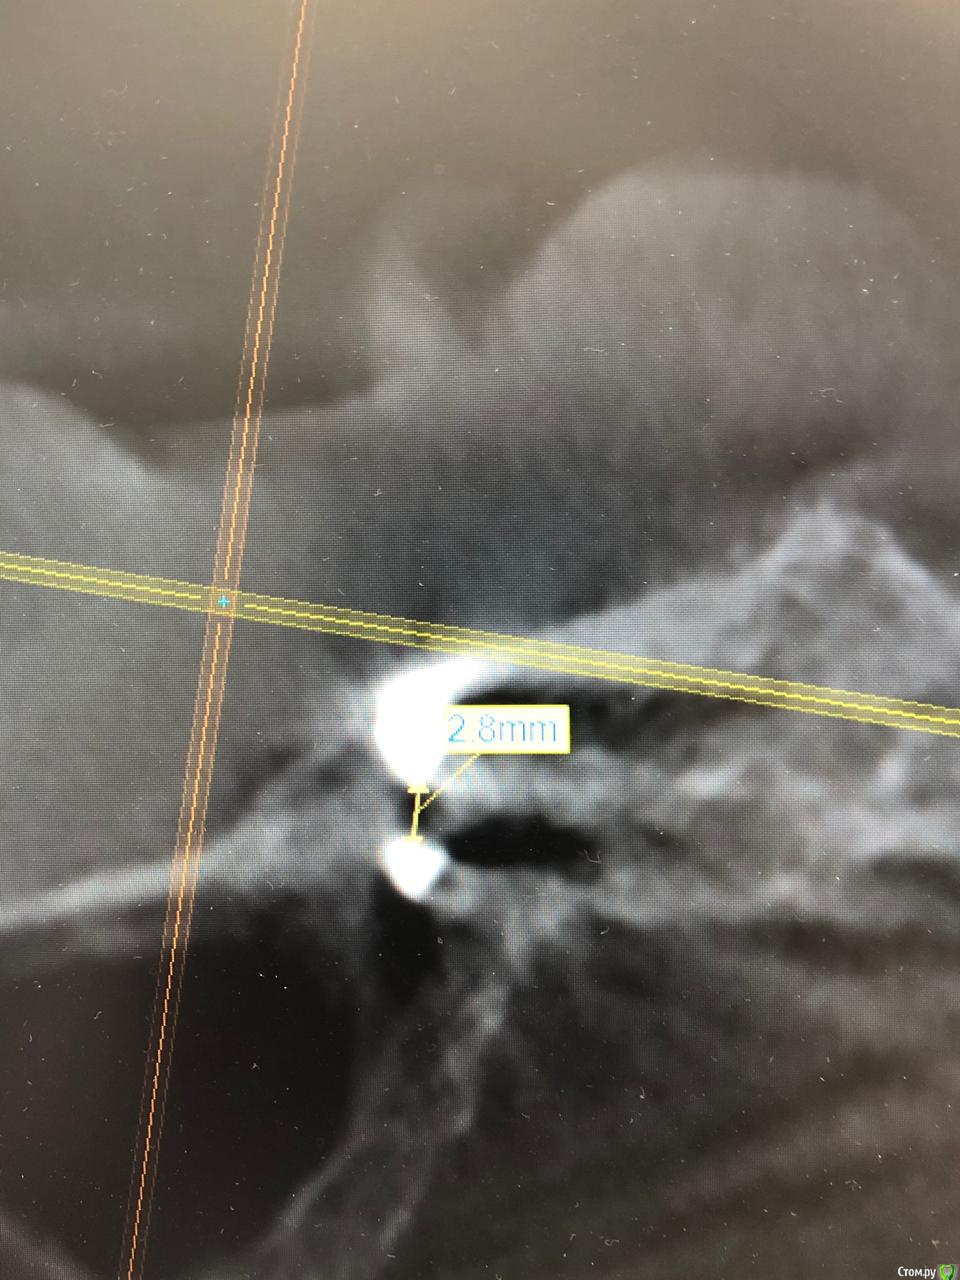

ALLA0105 Опубликовано 2 февраля, 2020 Автор Поделиться Опубликовано 2 февраля, 2020 Здравствуйте! Была у доктора, отправил на КТ ,чтобы определить точное расстояние. Он может по моему настоянию переставить имплант, но не считает это целесообразным. Говорит, что дает гарантию. Вот, что он мне прислал. Расстояние 2,5мм и 2,8 мм. Подскажите, а гарантию надо в договоре прописать? И на какое количество лет надо прописать гарантию , если соглашусь оставить все как есть? Ссылка на комментарий